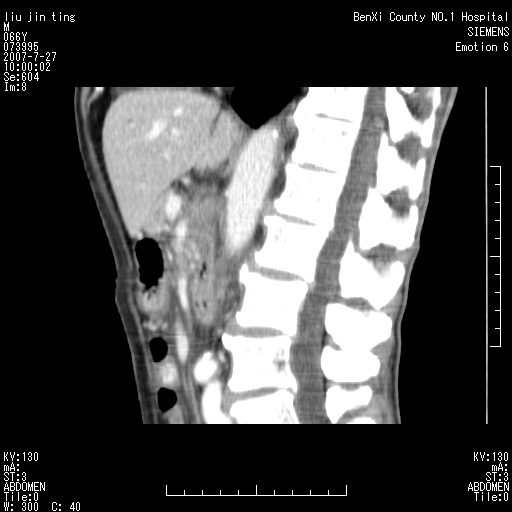

腹痛,背痛,无恶心呕吐,不黄,彩超示胰腺钩癌,ct扫描病灶平扫30-40hu,增强后动脉期40--60hu,静脉期50-68hu,真的是钩突上的么?您要试一试么?

动脉期

静脉期

沿着肠系膜上动脉呈匍匐性生长的软组织肿块,形态不规则,包绕肠系膜上动脉,呈明显强化,考虑来源于肠系膜的恶性肿瘤

沿着肠系膜上动脉呈匍匐性生长的软组织肿块,形态不规则,包绕肠系膜上动脉,呈轻-中度强化,考虑来源于肠系膜的恶性肿瘤。

支持!恶性纤维组织细胞瘤可能,与淋巴瘤及淋巴结转移鉴别(腹主动脉周围清晰,其他部位亦未见明显肿大淋巴结)。